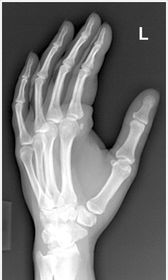

| PA Hand | ANATOMY: entire hand including 1'' of distal radius and ulna CRITERIA: equal concavity on either side of digits digits separated with no superimposition open joint spaces POSITIONING: CR perpendicular @ 3rd MCP joint |

| Oblique Hand | ANATOMY: entire hand including 1'' of distal radius and ulna CRITERIA: digits more concave to one side minimal overlap of 3rd-5th metacarpal shafts separation of the 2nd and 3rd metacarpals POSITIONING: CR perpendicular @ 3rd MCP joint |

| Lateral Hand | ANATOMY: entire hand including distal 1'' of radius and ulna superimposed CRITERIA: metacarpals and distal radius/ulna are superimposed thumb is free of superimposition *thumb in lateral position* open joint spaces POSITIONING: CR perpendicular @ 3rd MCP joint LAT Extension: foreign body localization LAT Flexion: phalanges |